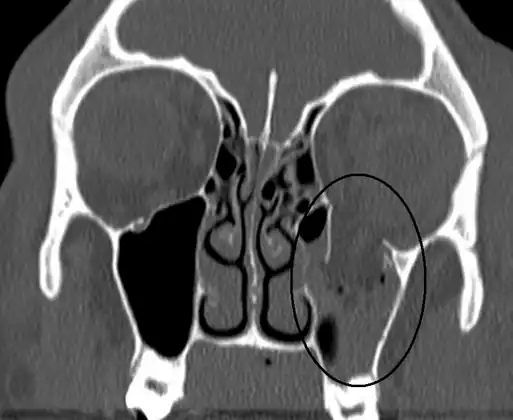

| An orbital blowout fracture involving the left orbital floor as seen on CT scan. | |